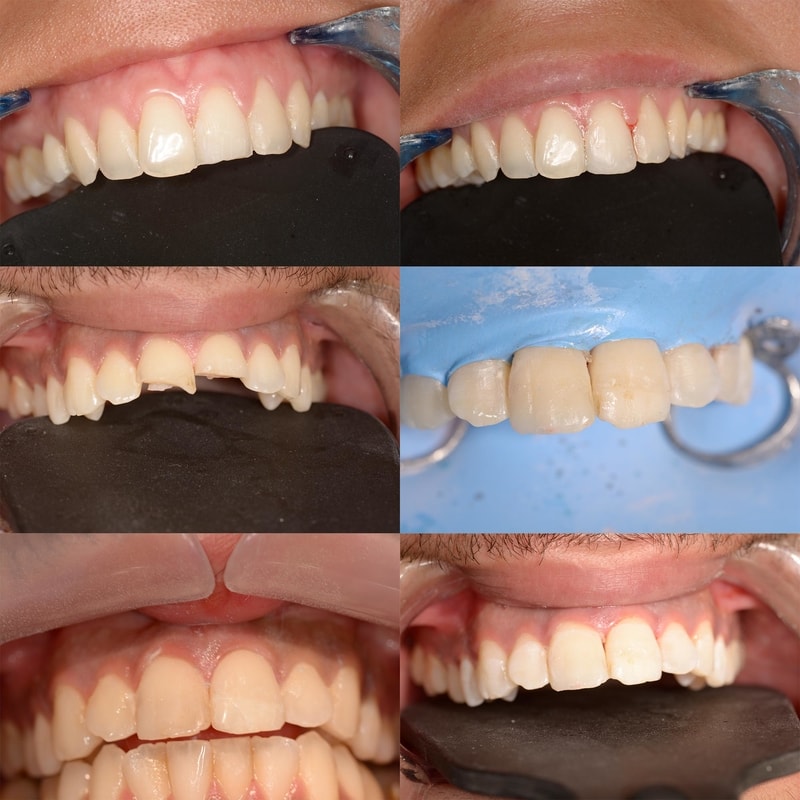

Esthétique du sourire DSD

Certains cas nécessitent une analyse de l’Esthétique du Sourire. Après une prise d’empreinte, l’appréciation de certaines mesures et la prise de clichés photographiques, nous étudierons la cohérence de votre sourire par rapport à certaines références, et vous proposerons, lorsque c’est nécessaire, une étude de votre cas. Elle sera accompagnée d’un projet esthétique virtuel.

Si ce projet est validé, nous validerons un essai (masque esthétique en bouche). En cas de validation, nous pourrons entamer les travaux esthétiques.

Cas numero 1 :

Situation Initiale

Etude du cas et proposition

Cas terminé

Cas numero 2 :